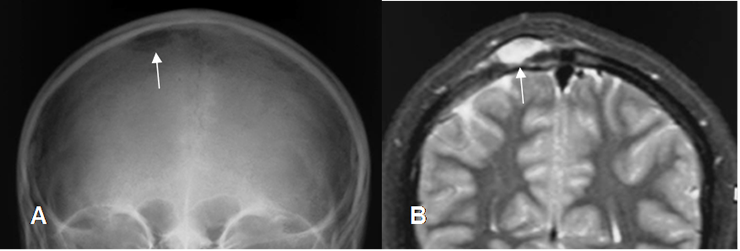

Fig 131. Granuloma Eosinófilo.

A: Rx AP, B: Rx lateral y C: TAC axial. Niño con lesión lítica y de bordes escleróticos, a nivel frontal izquierdo, por granuloma eosinófilo.